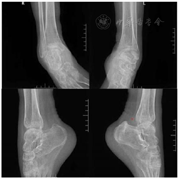

MMSE:20(扣分项:定向力8、回忆1、言语1);LOTCA 92分(扣分主要项目:定向力10、思维操作13);MoCA 13(扣分项:视空间与执行功能4、延时回忆5、句子复述1、语言相似性2、定向5);临床记忆检查记录表:MQ=33(很差<69)(指向记忆、联想学习、图像自由回忆、无意义图形再认、人像特点回忆均很差);RBMT行为记忆检查6分:重度障碍;数字广度测验正常;视觉图形记忆检查提示患者存在图形记忆障碍(图1)。Barthel指数:15(得分项:大便5、小便5、转移5)。